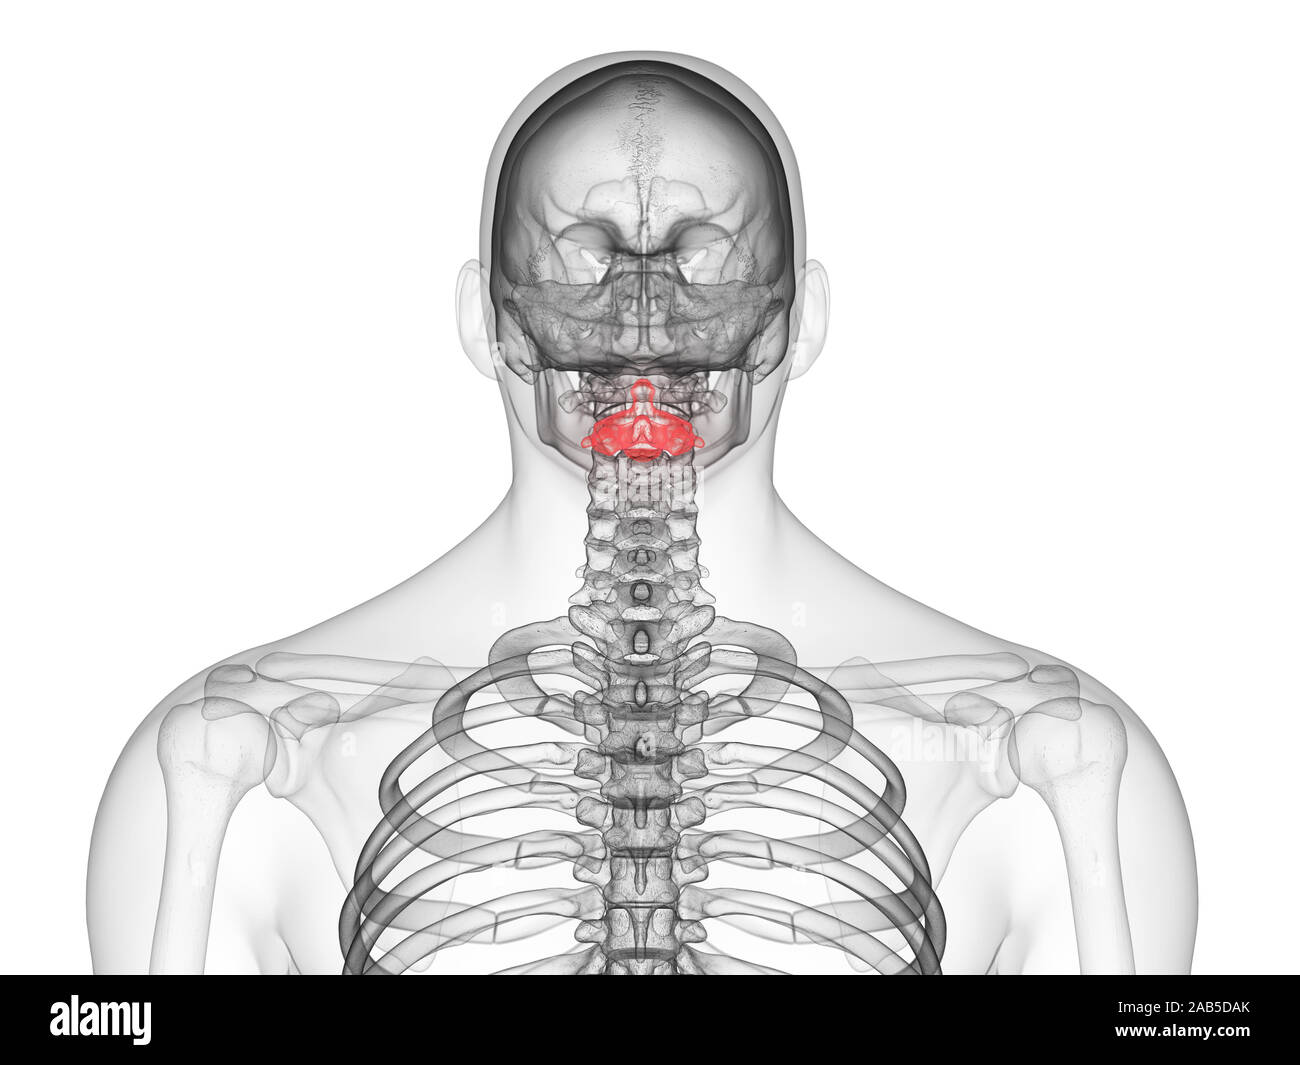

Https www alamy de bulletin der naturlichen histort museum geologie serie s andrews und y fernandez jalvo abb 16 a menschliche achse wirbel m 54042 zeigt die konformation des cut markierungen entlang der vorderen oberflache dies ist der bereich der befestigung der vorderen langsband und daruber hinaus die superior markierungen sind wahrscheinlich auf die ablosung der achse von der atlas und die hinteren markierungen aus um die loslosung der achse von der dritten halswirbel x 12 b schematische zeichnung des menschlichen schadel und oberen wirbel angezeigt um die disposition der beiden muskeln die an der inneren oberflache o image233869895 html (Dateityp jpg)

Bulletin Der Naturlichen Histort Museum Geologie Serie S Andrews Und Y Fernandez Jalvo Abb 16 A Menschliche Achse Wirbel M 54042 Zeigt Die Konformation Des Cut Markierungen Entlang Der Vorderen Oberflache